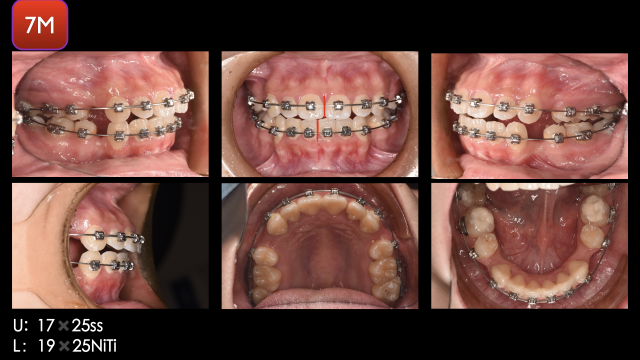

术前检查

术中治疗